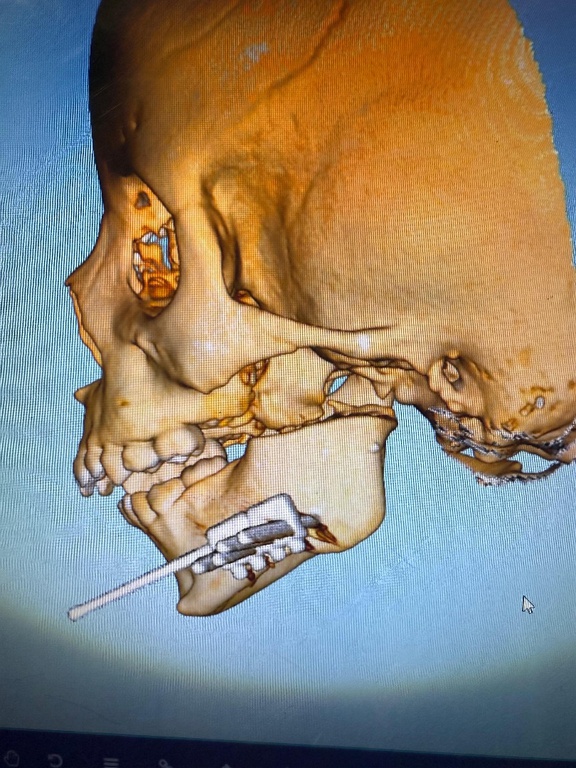

Campo Grande (MS) – Um procedimento cirúrgico inédito realizado na última terça-feira (05) no Hospital Universitário Maria Aparecida Pedrossian da Universidade Federal de Mato Grosso do Sul (Humap-UFMS), vinculado à Rede Ebserh, abriu novas possibilidades de tratamento para crianças com deformidades graves na mandíbula. A cirurgia marca a estreia do uso de distratores mandibulares extraorais na instituição, equipamento essencial para o manejo de alterações dentoesqueléticas em pacientes pediátricos.

A paciente foi uma criança de apenas quatro anos, diagnosticada com uma grave deficiência mandibular provocada por anquilose temporomandibular — condição em que a articulação entre a mandíbula e a base do crânio se funde, limitando a abertura bucal. O quadro se desenvolveu a partir de otites de repetição ainda nos primeiros meses de vida e comprometeu seriamente o crescimento mandibular, além de afetar funções essenciais como a respiração e a alimentação.

A cirurgia de alta complexidade mobilizou uma equipe multidisciplinar composta por profissionais das áreas de Cirurgia Bucomaxilofacial, Cirurgia Crânio-Maxilofacial, Anestesiologia e Cirurgia Torácica. Com a instalação do distrator mandibular extraoral, a mandíbula da paciente será expandida gradualmente nas próximas semanas, favorecendo o desenvolvimento facial, além da melhora progressiva da deglutição e da função respiratória.

Segundo os especialistas envolvidos, os distratores mandibulares extraorais são dispositivos indispensáveis no tratamento de deformidades causadas por traumas, infecções ou síndromes congênitas, como as de Pierre Robin, Goldenhar, Treacher Collins e Crouzon. Nessas situações, intervenções precoces são fundamentais para assegurar a permeabilidade das vias aéreas e o desenvolvimento adequado da face.